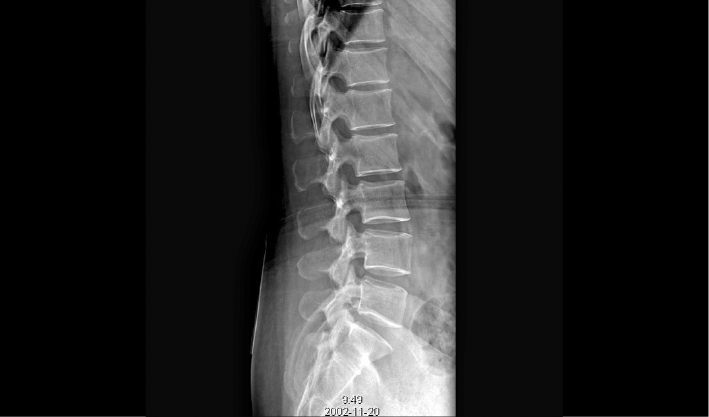

配合十軸智能全自動操控,實現六向跟蹤和一鍵自動擺位切換,融合高端配置,帶來一流的圖像,簡便操控,快捷流程,輔助醫生快速精準診斷。

消除線噪聲的同時不損失圖像細節,保持邊緣和分辨率,不會引入新偽影,增加圖像銳利度。

兩塊平板組合運用多種場景,減少平板插拔,簡化流程,提升拍攝效率。

管球無位移,消除運動誤差,提高拼接成功率。

重疊區域面積小,減少曝光次數,減少輻射劑量。

AEC自動曝光和影像均衡算法,保證拼接圖像統一亮度和對比度。